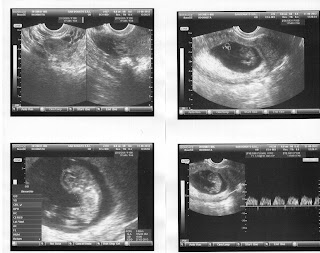

Echo 28 september 2012

We hebben vandaag de 14 weken echo gehad en het is waarschijnlijk een meisje:)))

Hier een filmpje van de echo. Het zijn eigenlijk meerdere aan elkaar geplakte filmpjes, want Fabio kon niet in 1 keer filmpen, omdat Luca intussen de spreekkamer aan het verkennen was. Dus je hoort Luca er af en toe doorheen.

Hier echo foto's van 7 weken: